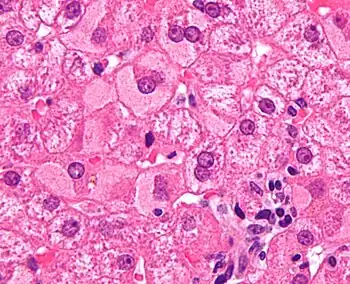

A previously undiagnosed liver disease may become evident first after autopsy. Following are gross pathology images: